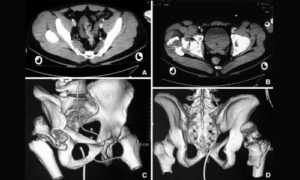

Мскт костей таза проводится с целью диагностики травм тазового кольца, опухолевых процессов, инородных тел в полости таза, патологии тазобедренных суставов, крестца и копчика. При необходимости тщательной оценки структур малого таза и мягких тканей рекомендуется использовать внутривенное контрастирование или прибегнуть к МРТ-исследованию.

Позволяет обнаруживать очаги уплотнения и разрежения, оценивать размеры, форму, расположение и распространенность патологических участков, выполнять трехмерную реконструкцию исследуемой зоны. Мскт костей таза проводится для уточнения характера повреждений при травмах таза (переломах, инородных телах).

Главное отличие процедуры от привычного рентгена — сканирование органических текстур человека в трехмерном изображении. Врач выстраивает 3D модель нужного участка организма. Шаг срезов не превышает одного-двух миллиметров, в зависимости от типа применяемого томографа. Высокая точность обеспечивает определение патологии даже при небольшом отклонении от стандартов.

МСКТ всех костей таза осуществляется без наркоза. Возможность получения сверхтонкого среза на аппарате последнего типа обеспечивает выявление недуга на ранних стадиях, что важно при диагностировании опухолевых процессов. Создание трехмерной модели костей таза помогает обнаружить все изменения и составить дальнейший план и прогнозы лечения.